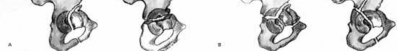

There are 5 simple and 5 associated fracture types according to the classification system created by Judet and Letournel. The key feature which distinguishes both column fractures from other associated types is that all articular segments are detached from the intact portion of the ilium, which remains attached to the sacrum through the SI joint.

Although the transverse plus posterior wall, T-shaped, and anterior plus posterior hemi-transverse fractures all show involvement of the anterior and posterior columns, they are not “both columns” because a portion of the

articular surface remains in its normal position, attached to intact ilium.

The intact ilium is responsible for the "spur sign" noted most prominently on the obturator oblique radiograph.

Illustration A demonstrates the 10 types of acetabular fractures as created by Judet and Letournel. Illustration B is an example of a both column acetabular fractures as seen on the obturator oblique radiograph.